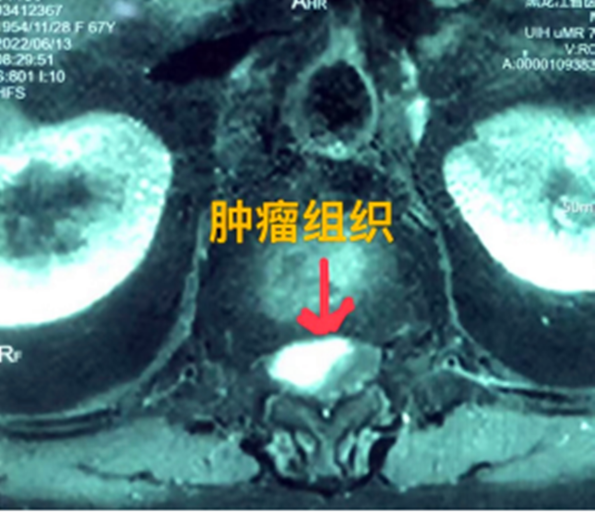

據(jù)省醫(yī)院神經(jīng)外一科陶宇醫(yī)生介紹,家住外地的張大娘最近總感覺(jué)雙下肢疼痛、無(wú)力,且排尿困難及便秘,伴有行走困難。時(shí)間長(zhǎng)了,張大娘病情逐漸加重,劇烈的疼痛甚至讓她無(wú)法完整入睡。在當(dāng)?shù)蒯t(yī)院,張大娘按腰椎肩盤(pán)突出接受治療,但未見(jiàn)好轉(zhuǎn),隨后進(jìn)行的胸椎MRI(核磁共振)檢查,結(jié)果不禁讓張大娘和家屬瞠目結(jié)舌,原來(lái)張大娘患的竟然是少見(jiàn)的脊髓腫瘤。

張大娘住進(jìn)了黑龍江省醫(yī)院神經(jīng)外一科,該科孫國(guó)章主任醫(yī)師熱情地接待了張大娘,并邀請(qǐng)骨外一科專(zhuān)家共同為她進(jìn)行了聯(lián)合會(huì)診。發(fā)現(xiàn)張大娘病情十分復(fù)雜棘手,脊髓腫瘤體積較大,充滿(mǎn)髓腔且神經(jīng)已經(jīng)完全受壓,需要手術(shù)來(lái)完整切除。同時(shí)還發(fā)現(xiàn)張大娘的胸腰部曾受過(guò)兩次外傷,伴有多處骨折,這對(duì)接下來(lái)的手術(shù)操作帶來(lái)一定影響。